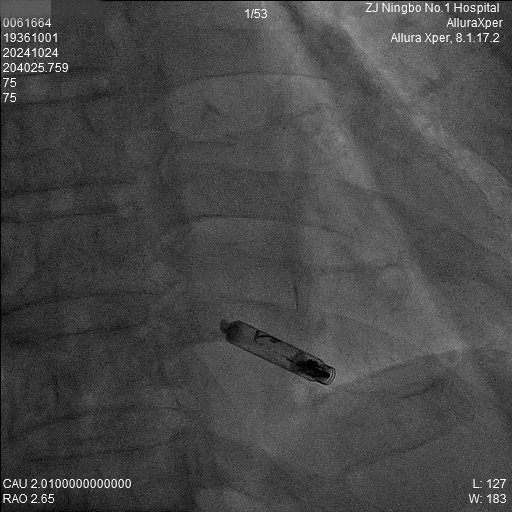

3.调弯进入右室低位间隔后造影,位置理想。左前造影明确贴靠间隔。

b) LAO